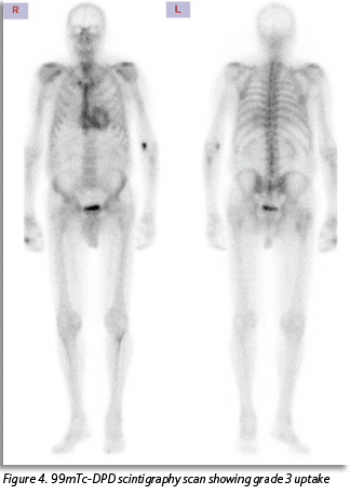

MRI showed rapid washout of gadolinium post-contrast with subendocardial late gadolinium enhancement suggestive of amyloidosis. Instead of being referred for endomyocardial biopsy this patient underwent a 99mTc-DPD scintigraphy scan. This revealed radioisotope uptake consistent with amyloidosis (see Figure 4).

(click to enlarge)

This case also illustrates the improvement in diagnostic modalities for ATTR-CM. Bone-avid radiotracer scintigraphy technology in the form of a 99mTc-DPD scan, is a non-invasive and readily available imaging modality. Patients who test negative for AL amyloid can avoid an endomyocardial biopsy. In the absence of an abnormal serum free light chain ratio or detectable monoclonal proteins, the specificity of bone scintigraphy for ATTR-CM is 100%.11 The sensitivity of the DPD scan for detecting amyloid deposits is > 99%.11 The timely diagnosis of disease in this case was crucial, given the potential utility of disease-modifying TTR-specific therapies. Timely and accurate diagnosis also ensures tailored management of heart failure, avoiding poorly tolerated treatments like vasodilators or negative inotropic/chronotropic agents. Additionally, it allows clinicians to be vigilant for other complications of amyloidosis that may arise.